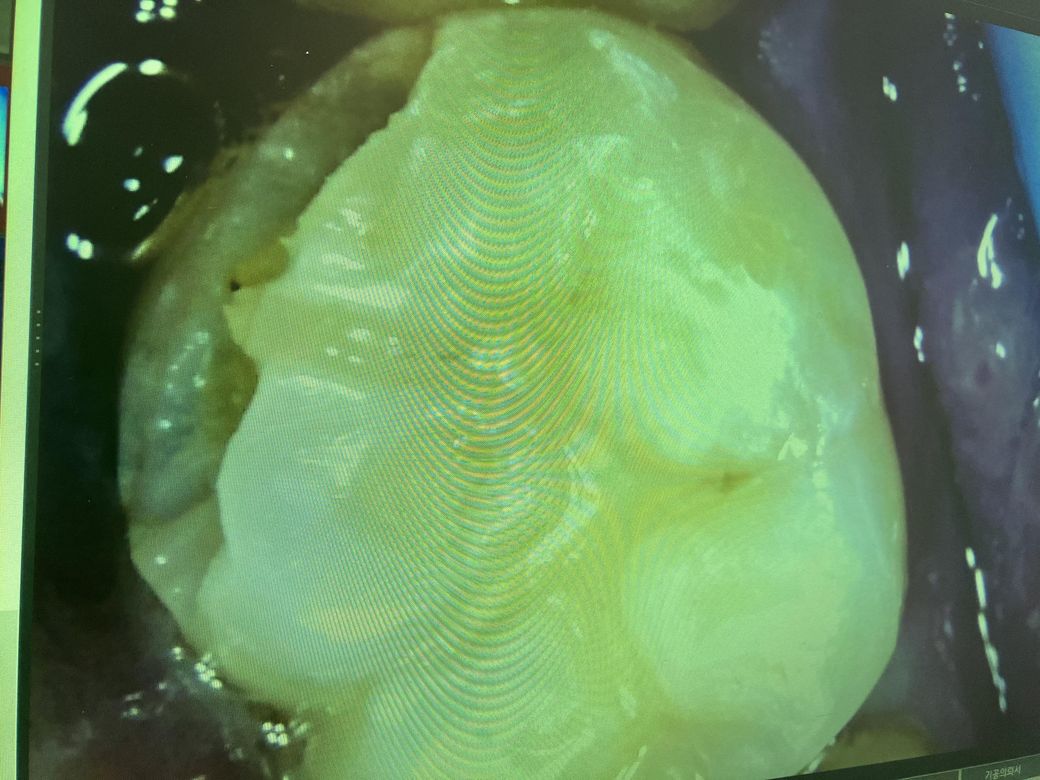

• 1번 째 사진

자르코니아? 크라운 작은어금니 하나 했습니다. 충치가 깊어서 크라운했습니다. 그런데 박고 7일있다 무슨 순살치킨먹다가 반으로 두동강나면서 옆에 큰어금니를 씹는바람에 큰어금니 위쪽도 조금 부셔졌어요 ... 너무 깊에 부셔진건 아니고 위에만 벗겨진거같은데 범랑질은 아닌거같아요 시리고 아픈거보니 그래서 내원을 햇는데 또 크라운을 권유하더라구요 .. 이건 인레이 레진으로 할수가없다고 생각보다 많이 깨진거라고 ... 쌩니를 그것도 어금니 두개나 이렇게 되서 이게 맞는건가 싶고 과잉진료가 아닌건가 싶기도하고 유튜브나 다른거보면 훨씬많이 부셔지고 해도 신경만 괜찮으면 레진이나 인레이로 때우던데 그렇게 심하게 부셔진것도아닌데 또 갈아서 임시치아 씌워놨네요 ... 도대체 뭘까요 ? 충치가 있어서 깨진게아니라 크라운이 떨어지면서 그걸 씹는바람에 깨진겁니다 . 말로는 옆면이고 이게 너무 오래되서 전체적으로 약해져있다.. 제가볼땐 전혀그런 느낌 그런걸 느끼질 못햇는데.. 도통 이해가 가질않네요 저번 같은곳에서 충치가 깊어 인레이를 했는데 그것보다 범위가 훨씬작은데 크라운이 왼말인가요..